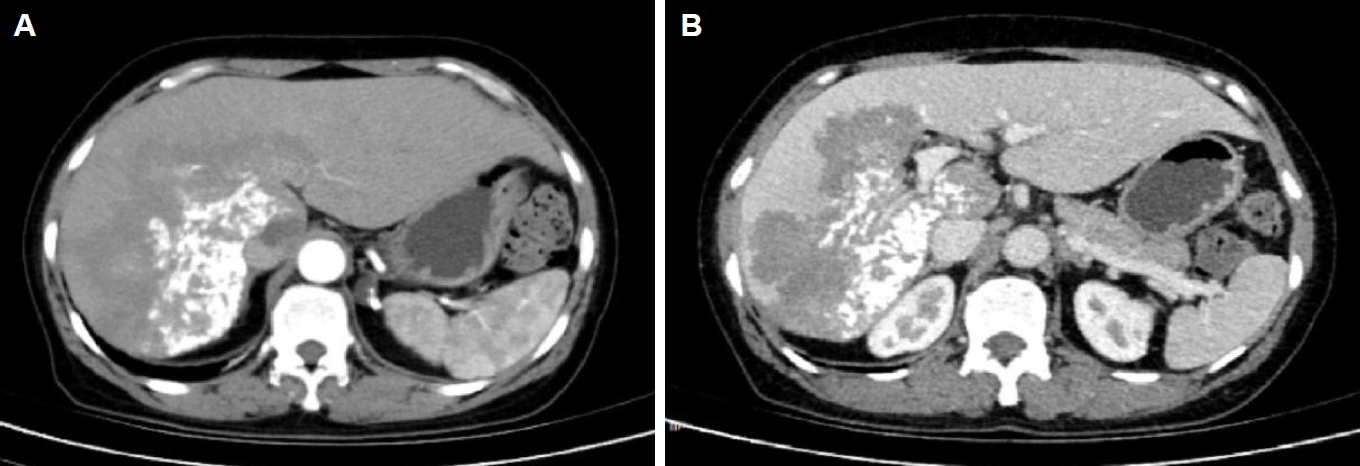

Ultrasound showed a heterogeneous hyperechoic mass (7.8×5.5 cm) with unclear borders in liver segments S4, S7, and S8 (Fig. 1). Computed tomography suggested a large, poorly defined mass with mixed density and patchy calcifications (maximum cross-sectional area 15.11×11.29 cm) in the liver. No enhancement was observed in dynamic contrast imaging. A low-density lesion in the left adrenal gland showed no enhancement (Fig. 2A). The right portal vein was narrowed. The right and middle hepatic veins were partially obscured in the portal venous phase (Fig. 2B). The presence of a large, infiltrative mass with heterogeneous density and irregular calcifications is a recognized, though not universal, imaging presentation of advanced alveolar echinococcosis, which can mimic malignancy.

Fig. 2.

Abdominal computed tomography (CT) of the liver. (A) Arterial phase CT demonstrates a large hypodense occupying lesion in the liver with patchy hyperdense areas, showing no enhancement. A non-enhancing hypodense lesion is observed in the left adrenal region. (B) Portal venous phase CT reveals stenosis of the right portal vein branch within the lesion area, with partial obscuration of the right and middle hepatic veins.

Fig. 2. Abdominal computed tomography (CT) of the liver. (A) Arterial phase CT demonstrates a large hypodense occupying lesion in the liver with patchy hyperdense areas, showing no enhancement. A non-enhancing hypodense lesion is observed in the left adrenal region. (B) Portal venous phase CT reveals stenosis of the right portal vein branch within the lesion area, with partial obscuration of the right and middle hepatic veins.